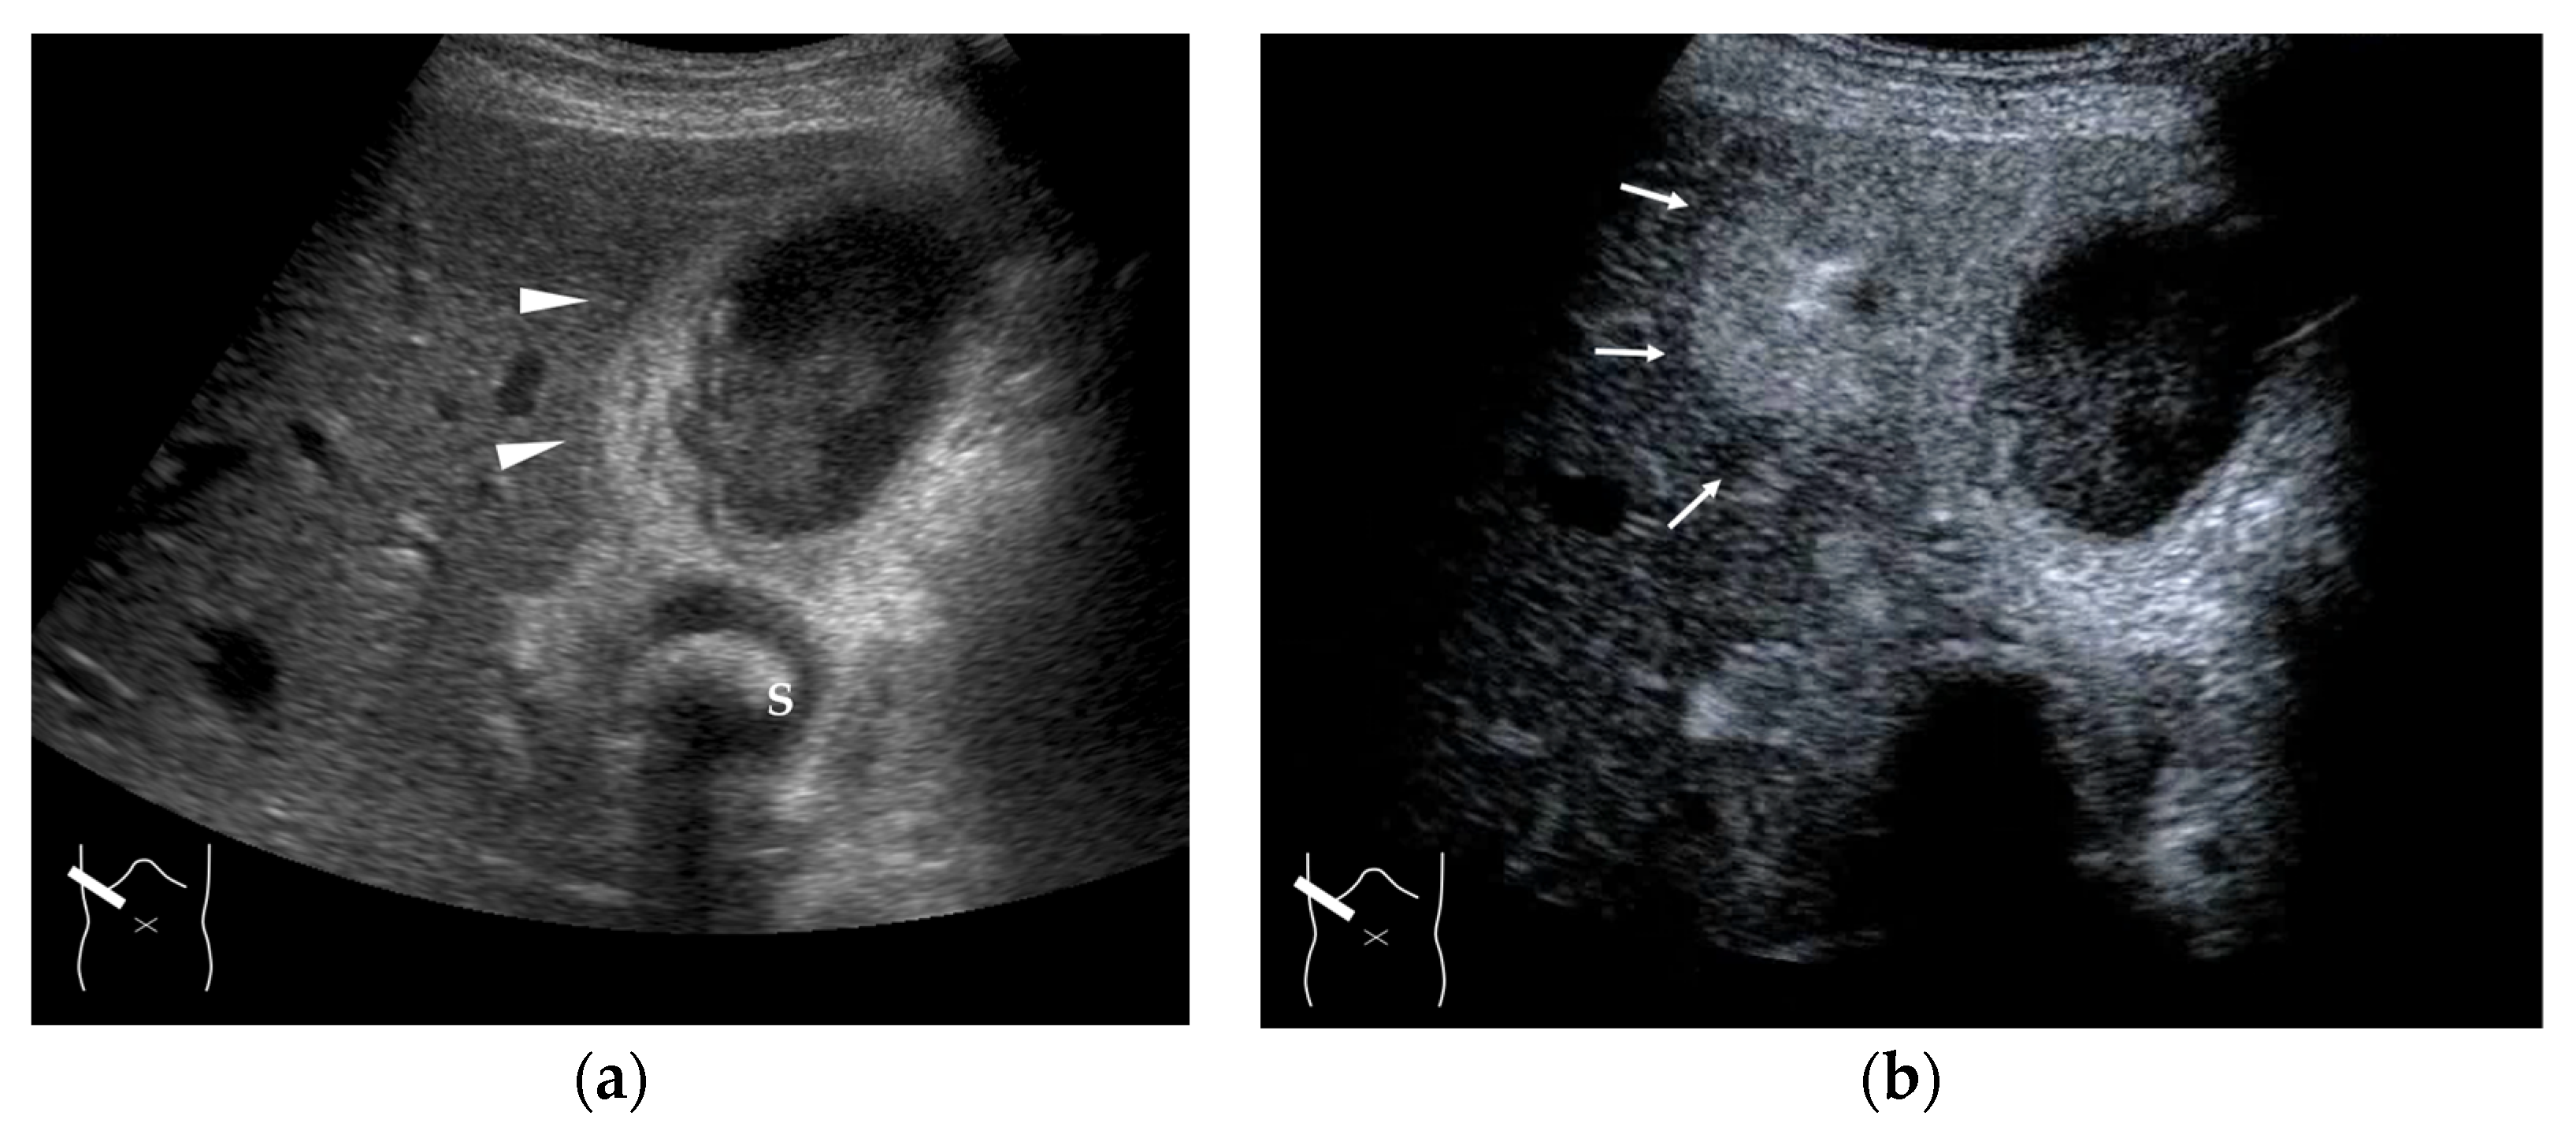

4.4. Hemodynamic Abnormalities in Liver Abscess

4.5. Hemodynamic Abnormalities in Liver Necrosis

- Lardière-Deguelte, S.; Ragot, E.; Amroun, K.; Piardi, T.; Dokmak, S.; Bruno, O.; Appere, F.; Sibert, A.; Hoeffel, C.; Sommacale, D.; et al. Hepatic abscess: Diagnosis and management. J. Visc. Surg. 2015, 152, 231–243. [Google Scholar] [CrossRef]

- Morita, M.; Ogawa, C.; Omura, A.; Noda, T.; Kubo, A.; Matsunaka, T.; Tamaki, H.; Shibatoge, M.; Seno, H.; Minami, Y.; et al. The efficacy of Sonazoid-enhanced ultrasonography in decision-making for liver abscess treatment. Intern. Med. 2020, 59, 471–477. [Google Scholar] [CrossRef]

- Kuroda, H.; Abe, T.; Fujiwara, Y.; Nagasawa, T.; Suzuki, Y.; Kakisaka, K.; Takikawa, Y. Contrast-enhanced ultrasonography-based hepatic perfusion for early prediction of prognosis in acute liver failure. Hepatology 2021, 73, 2455–2467. [Google Scholar] [CrossRef]